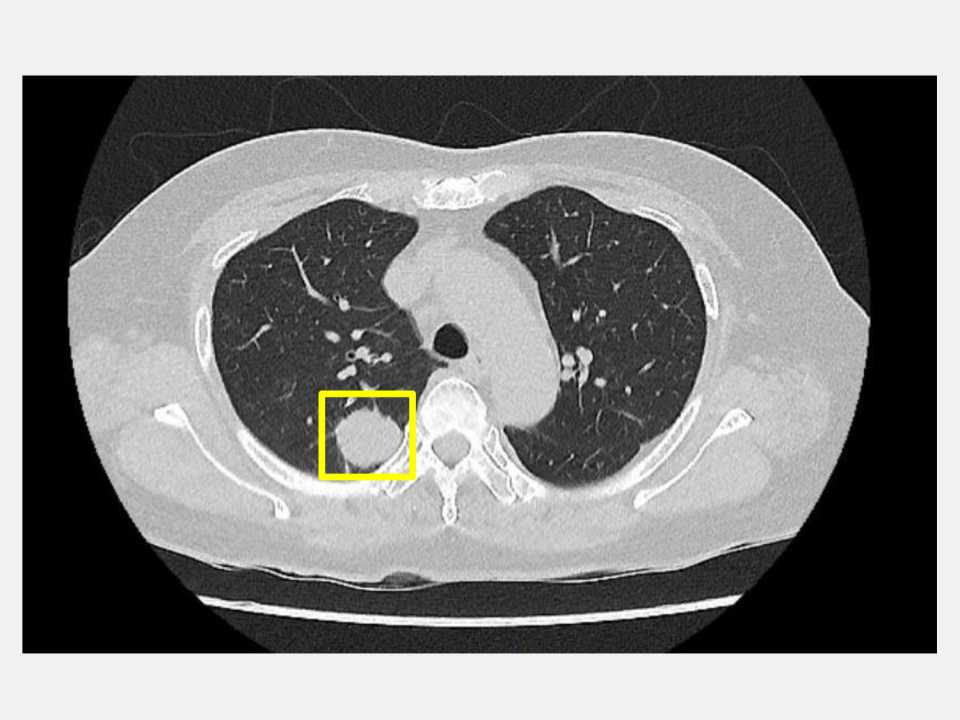

【記者 林珠平 台中報導】50歲的吳先生平時生活作息規律,從不抽菸,也沒有肺癌家族史,原以為自己身體健康的他在一次健康檢查中,經由低劑量電腦斷層(LDCT)意外發現右側肺部有一顆約2公分大小的腫瘤。吳先生前往仁愛長庚合作聯盟醫院(大里仁愛醫院)尋求醫療專業協助,經由胸腔暨心臟血管外科林宜右醫師詳細評估後,建議進行肺臟腫瘤切除手術,並且採用目前先進的「單孔達文西機器人微創手術」技術,在三天內順利出院。

林宜右醫師表示,傳統肺臟腫瘤切除是以開胸手術為主,需要大範圍切開胸壁,不僅傷口大、疼痛明顯,恢復期也長。隨著醫療科技進步,微創胸腔鏡手術逐漸成為主流,大幅減少了手術創傷。近年來,更有達文西機器人手術的發展,透過高解析立體影像與靈活機械手臂,醫師能更精準地進行肺臟腫瘤切除,同時保留更多健康肺組織,提高手術安全性與完整性。一般傳統達文西手術需開四至五個小傷口以置入器械,但林宜右醫師及團隊運用單孔達文西機器人技術,僅需約4公分的單一小切口即可完成整個手術,大幅減輕病患術後疼痛與不適。

吳先生在充分了解手術方式後,選擇接受由林宜右醫師主刀的單孔達文西肺部腫瘤切除手術。手術過程順利,僅在右側胸壁開設一個小傷口,透過主刀醫師執行單孔達文西手術,精細操作,成功完整切除腫瘤。吳先生術後的疼痛感大幅減輕,不僅無須承受傳統手術的大範圍創傷,恢復速度也比預期更快,手術隔天便可下床活動。

林宜右醫師說,現代醫療的進步,是希望讓每一位病人都能以最小的負擔,獲得最完善的治療。並提醒,肺癌初期多無明顯症狀,凡是有吸菸史或家族病史的人,應定期接受低劑量電腦斷層篩檢(LDCT),及早發現及早治療,才能守護健康。